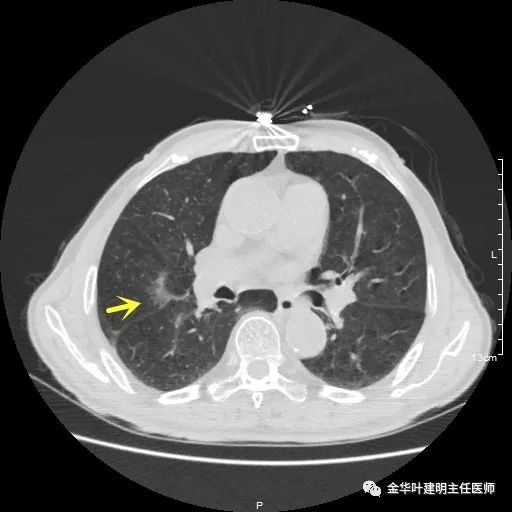

以上示右中叶病灶4。也是囊腔型病灶,病灶大,囊壁是磨玻璃密度,亦是较为典型的囊腔型肺癌影像。单病灶看,需中叶切除来治疗,因病灶3的存在,中叶切除可同时解决病灶3与病灶4。